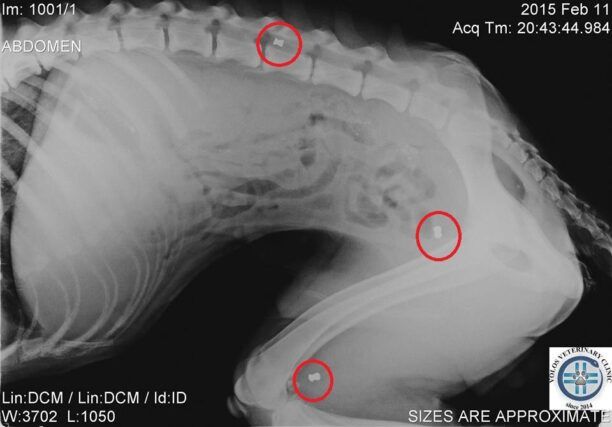

Το ζώο ήταν τόσο εξασθενημένο, τόσο υποσιτισμένο και αφυδατωμένο που σε κάθε δύο βήματα έπεφτε. Σηκωνότανε με δυσκολία ενώ από την μύτη του έσταζε αίμα. Τελικά η κοπέλα με τη βοήθεια ενός ακόμα ευαίσθητου νεαρού του κτηνιάτρου Φιλήμονα Διαμαντή κατάφερε να το πιάσει. Το σκυλί μεταφέρθηκε στο κτηνιατρείο του κ. Διαμαντή και οι ακτινογραφίες έδειξαν ότι στο κορμί του έφερε και τρία σφαιρίδια από αεροβόλο όπλο.

Το εκπληκτικότερο όμως, που είναι και ο λόγος για τον οποίο γράφω αυτό το άρθρο, είναι ότι στις ακτινογραφίες που του έγιναν με έκπληξη είδαμε να φαίνονται οι σκιές από τρία μικρά βόλια αεροβόλου όπλου σε διάφορα σημεία του σώματος του.